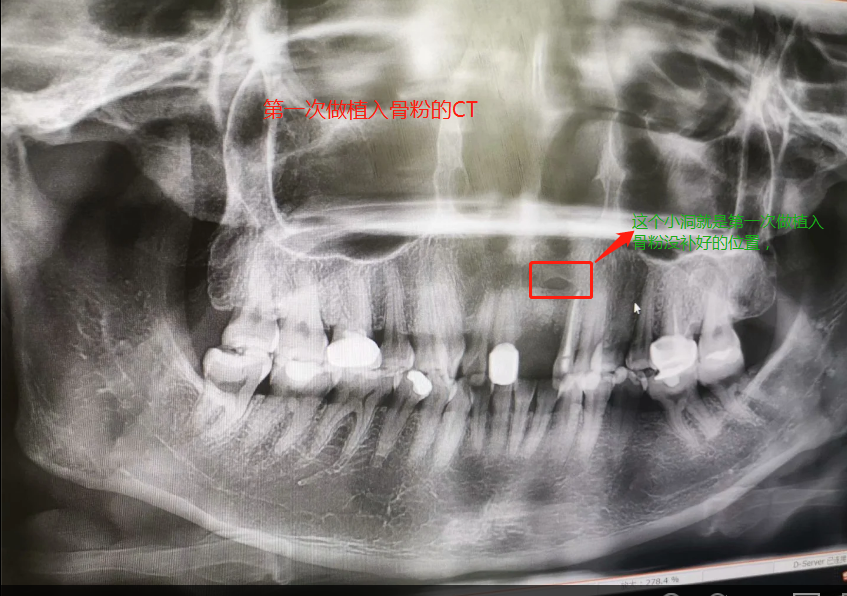

第一次做完植入手術(shù)后拍的CT

2019年7月27日做了種植骨粉手術(shù),在醫(yī)院要等半個(gè)小時(shí)留意一下是否有出血情況,沒有就可以回家休息。做手術(shù)是自己一個(gè)人坐地鐵來回的,勇敢吧。第一天嘴里都是血,第二第三天也是,臉也腫起來,也會(huì)有一點(diǎn)點(diǎn)骨粉掉出來,我那幾天都是喝粥和喝湯,第四天才敢吃飯,第七天傷口就好了,可以帶上臨時(shí)假牙,因?yàn)槲沂巧项€門牙,上顎骨頭密度沒有那么好,正常要等4個(gè)月左右,我的骨粉還是種植的,不是自身的骨頭,所以必須要等半年才能種種植牙。等到2020年1月26日去種植牙根的時(shí)候,那個(gè)主任已經(jīng)調(diào)去別的分店,第一次補(bǔ)完骨粉我就發(fā)覺里面還有個(gè)小洞,問醫(yī)生里面為什么有個(gè)洞的,醫(yī)生說沒事的。我打算去分店種植牙齒的,以為跟我那個(gè)醫(yī)生會(huì)比較了解我情況,后來那個(gè)的助理叫我不要去分店弄了,在這里安排個(gè)專家給我看。經(jīng)過專家的診斷,我還有個(gè)洞沒有補(bǔ)到骨粉,需要再做個(gè)補(bǔ)骨粉手術(shù)后等半年看看情況能不能種牙再說。我聽了真想哭起來,大門牙好不容易空半年可以種牙了,結(jié)果還要我補(bǔ)骨粉,還要等那么長(zhǎng)時(shí)間。經(jīng)過跟這家醫(yī)院醫(yī)生溝通和別的門診醫(yī)生回答,決定還是回到這家醫(yī)院做修復(fù),跟助理談了價(jià)格,他說就收取800元,補(bǔ)0.5克骨粉。于是就開始了第二次手術(shù),第一次手術(shù)補(bǔ)了0.5克骨粉(2個(gè)單位,0.25克為一個(gè)單位),第二次補(bǔ)了0.75克骨粉,本來是0.5克骨粉,醫(yī)生做手術(shù)的時(shí)候說還有點(diǎn)間隙,還需要0.25克骨粉,問我要不要加,我說加,就算要另外收費(fèi),我也要加,我的牙齒受的折磨太多了。我要好好弄好這顆牙齒,就收了800元,也沒有額外收0.25克的骨粉錢。我在這家口腔醫(yī)院花了6800元種植骨粉,第二次骨粉植入傷口比較大,醫(yī)生說恢復(fù)期要12天,確實(shí)7天傷口還是沒有恢復(fù)的很好。而且今年1月底爆發(fā)疫情,1月31日領(lǐng)導(dǎo)就讓我們上班,我們公司是做醫(yī)療設(shè)備。傷口都沒有完全康復(fù)就堅(jiān)持上班了。